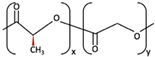

| 1 | PGA |  [39] [39] | High [29] | High [59] | − [59] | 4–12 months [60] | Tissue engineering. Drug-delivery systems [61] | |

| PLA | PLLA |  [62] [62] | High [63] | High [64] | − [51] | > 3.5 years [65] | Tissue engineering. Drug-delivery systems. Fixation devices [66] | |

| PDLA |  [62] [62] | High [63] | High [64] | − [64] | Longer than PLLA [34] | Tissue engineering. Drug-delivery systems, [66] | ||

| PDLLA |  [62] [62] | Lower than PLLA [37] | High [64] | − [64] | 12–30 months [37] | Tissue engineering. Drug-delivery systems [66] | ||

| 2 | PLLA/PGA |  [67] [67] | High [37] | High [68] | − [50] | 12–18 months [44] | Tissue engineering. Drug-delivery systems. Fixation devices [66] | |

| 3 | u-HA/PDLLA | Ca10(PO4)6(OH)2 +  | Low [54] | High [55] | + [56] | 12–18 months [69] | Tissue engineering. Fixation devices [70] | |

| u-HA/PLLA | Ca10(PO4)6(OH)2 +  | Higher than PLLA [19] | High [19] | + [19] | > 5 years [49] | Tissue engineering. Fixation devices [70] | ||

| 4 | u-HA/PLLA/PGA | Ca10(PO4)6(OH)2 +  | Similar to u-HA/PLLA [71] | High [72] | + [71] | 2–3 years [73] | Tissue engineering. Fixation devices [73] | |